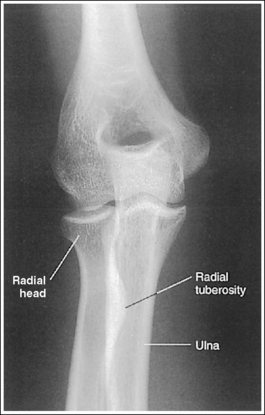

The elbow is positioned in an AP projection. The medial and lateral humeral epicondyles are demonstrated in profile at the extreme medial and lateral edges of the distal humerus, and the radial head is superimposed over the lateral aspect of the proximal ulna by approximately 0.25 inch (0.6 cm). The coronoid process is demonstrated on end.

• An AP projection of the elbow is obtained by supinating the patient's hand and externally rotating the forearm and humerus until an imaginary line drawn between the humeral epicondyles is parallel with the IR (Figure 4-67). This positioning places the proximal radius anterior to the ulna.

The radial tuberosity is demonstrated in profile medially, and the radius and ulna are parallel.

• The alignment of the radius and ulna is determined by the position of the humerus and the wrist. When the humerus is positioned with the humeral epicondyles parallel with the IR, the radial and ulnar relationship can be adjusted with wrist rotation. For an AP projection of the elbow, the hand and wrist should also be positioned in an AP projection by supinating the hand. This positioning places the radial tuberosity medially in profile and eliminates crossing of the radius and ulna. As the hand and wrist are pronated, the radius crosses over the ulna, and the radial tuberosity is rotated posteriorly, out of profile (see Image 77).

The proximal forearm is positioned in an AP projection. The radial head is superimposed over the lateral aspect of the proximal ulna by approximately 0.25 inch (0.6 cm). If included on the IR, the medial and lateral humeral epicondyles are demonstrated in profile at the extreme medial and lateral edges of the distal humerus.

• An AP proximal forearm projection is obtained by palpating the humeral epicondyles and aligning them parallel with the IR, placing the proximal radius anterior to the ulna (see Figure 4-59).